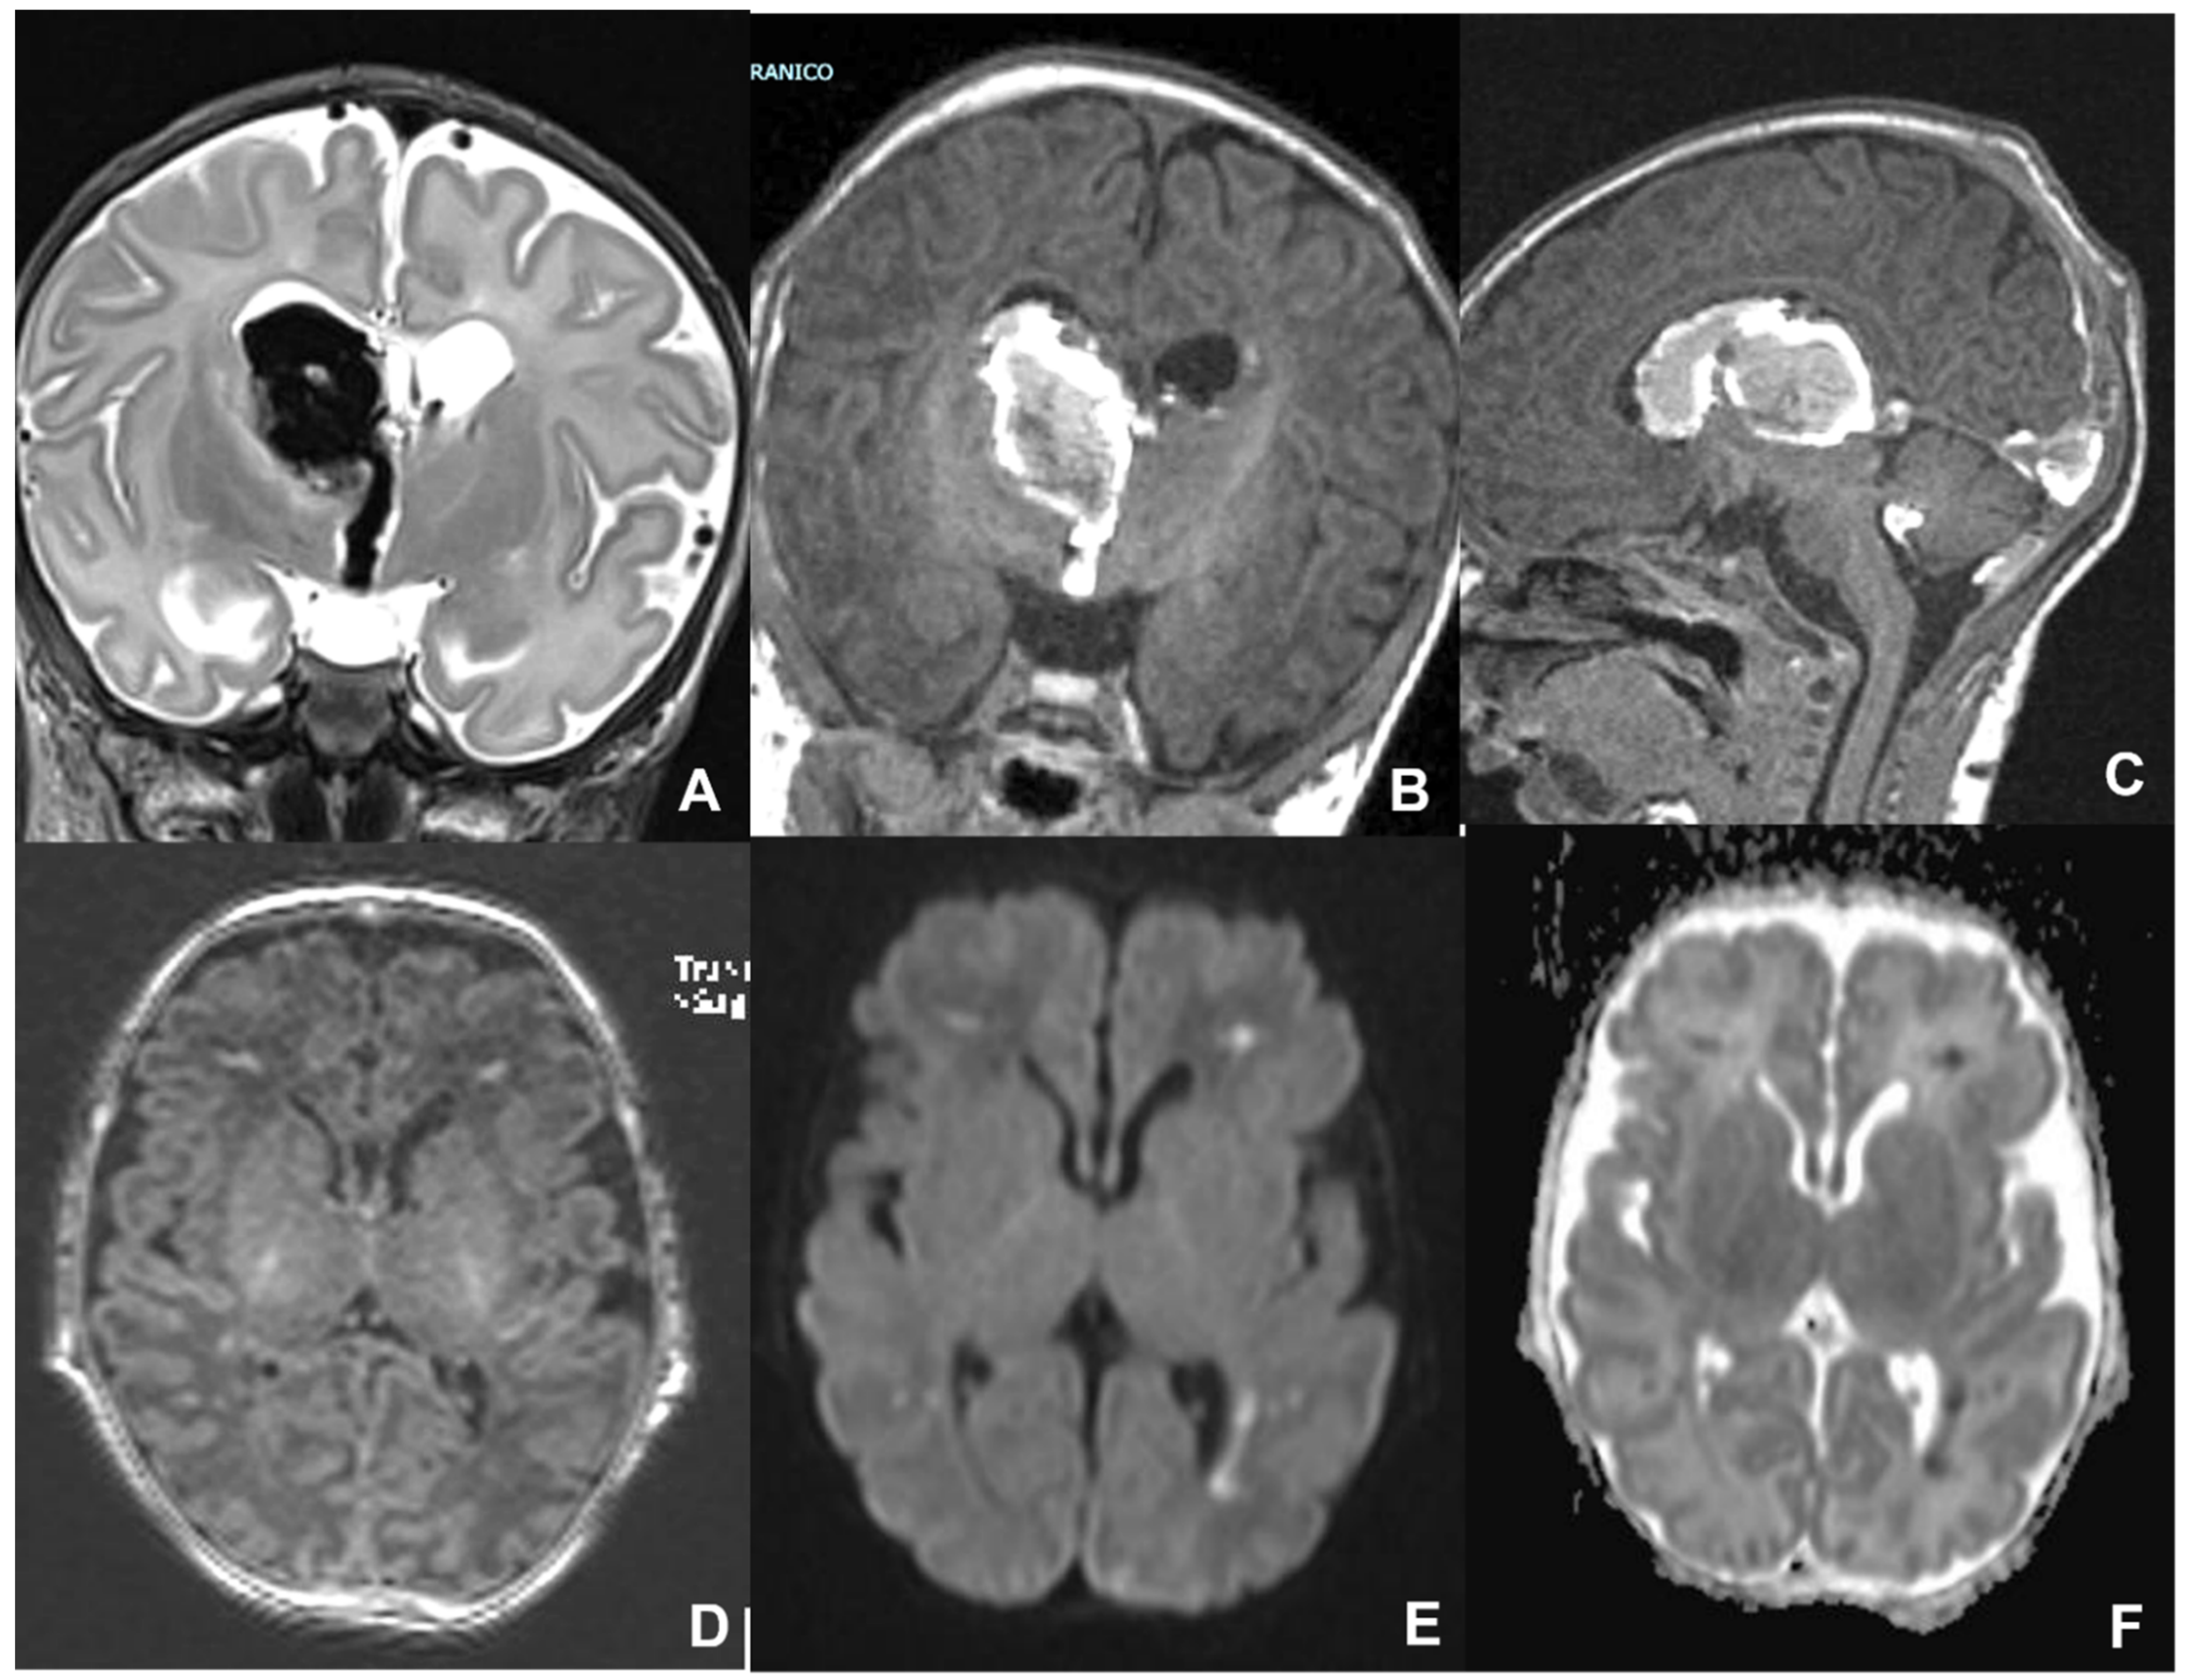

- Baskin, H.J.; Hedlund, G. Neuroimaging of herpesvirus infections in children. Pediatr. Radiol. 2007, 37, 949–963. [Google Scholar] [CrossRef]

- Kubota, T.; Ito, M.; Maruyama, K.; Kato, Y.; Miyajima, Y.; Ogawa, A.; Kuno, K.; Okumura, A.; Watanabe, K. Serial diffusion-weighted imaging of neonatal herpes encephalitis: A case report. Brain Dev. 2007, 29, 171–173. [Google Scholar] [CrossRef]

- Okanishi, T.; Yamamoto, H.; Hosokawa, T.; Ando, N.; Nagayama, Y.; Hashimoto, Y.; Maihara, T.; Goto, T.; Kubota, T.; Kawaguchi, C.; et al. Diffusion-weighted MRI for early diagnosis of neonatal herpes simplex encephalitis. Brain Dev. 2015, 37, 423–431. [Google Scholar] [CrossRef]

- Wong, A.M.; Yeh, C.H.; Lin, J.J.; Liu, H.L.; Chou, I.J.; Lin, K.L.; Wang, H.S. Arterial spin-labeling perfusion imaging of childhood encephalitis: Correlation with seizure and clinical outcome. Neuroradiology 2018, 60, 961–970. [Google Scholar] [CrossRef]

- Soares, B.P.; Provenzale, J.M. Imaging of Herpesvirus Infections of the CNS. AJR Am. J. Roentgenol. 2016, 206, 39–48. [Google Scholar] [CrossRef]